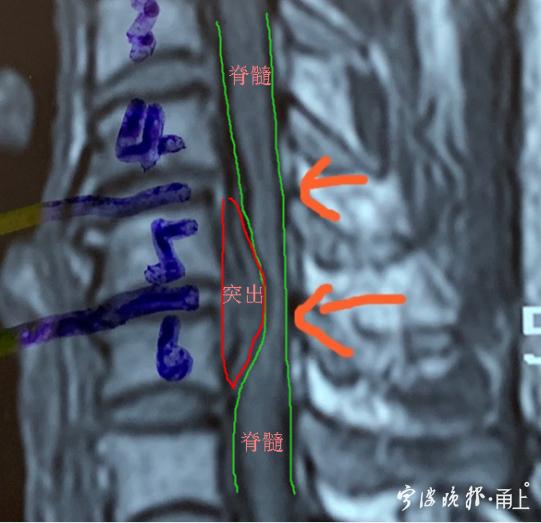

術前圖片可以明顯看到椎管狹窄,脊髓嚴重受壓并伴有變性。

經(jīng)一段時間的保守用藥治療,小趙的病情不見好轉。于是,他被轉入寧波市第一醫(yī)院神經(jīng)外科。入院后,該科脊柱脊髓組韋益停副主任醫(yī)師認真分析了小趙的病情,發(fā)現(xiàn)了更糟糕的情況:除了頸部5/6椎間盤突入髓核的情況,還存在頸部4/5椎間盤的突出,硬脊膜也出現(xiàn)鈣化情況。